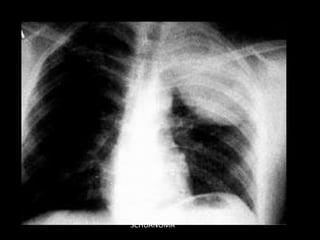

MEDIASTINO POSTERIOR

NEUROGENICO

SCHUANOMA

NEUROGENICOS

• Ubicación: mediastino posterior

• Edad: sin predominio

• Clínica: dolor, síndrome medular

• Diagnóstico:

– RMN para ver invasión de canal raquídeo

• Tratamiento: cirugía